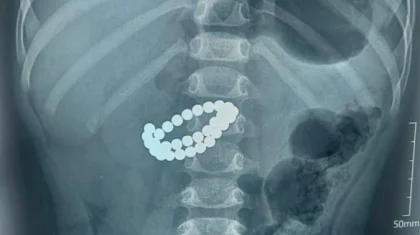

Алматыда екі жасар бала 31 магнит жұтып қойған